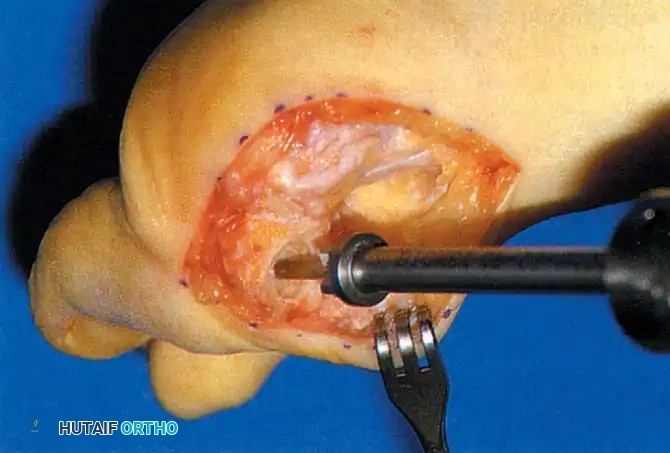

• Using a Freer elevator or a small osteotome for its strength, mobilize the fi bular sesamoid (Fig. 78-31A to C). This may be diffi cult in elderly patients with signifi cant deformity and adherence of the sesamoid to the metatarsal head. Lift the metatarsal dorsally for exposure (Fig. 78-31D and E).

Fig. 78-31 Excision of fi bular sesamoid in modifi ed Keller procedure. With base of proximal phalanx removed and medial eminence excision, exposure of fi bular sesamoid is not as diffi cult from medial incision. A, Operative photograph showing elevation of fi rst metatarsal with strong two-tooth retractor and use of small osteotome to mobilize fi bular sesamoid and lateral capsuloligamentous (frequently contracted) structures. Osteotome is between metatarsal head and lateral sesamoid. When mobilization of fi bular sesamoid is complete, entire sesamoid is visible for excision. Note chondromalacia of tibial sesamoid articular surface medial to osteotome. B, Fibular sesamoid has been excised, and lateral capsular structures and conjoined tendon (in forceps) have been released. Neurovascular bundle to lateral side of hallux is adjacent to these structures. C, Diagrammatic representation of modifi ed Keller procedure. By excising fi bular sesamoid, valgus moment of conjoined tendon of fl exor hallucis brevis and adductor hallucis no longer pulls fl exor hallucis longus tendon laterally (carrying hallux with it) through capsulosesamoid plantar plate and pulley system. D, Metatarsal head must be lifted dorsally to excise fi bular sesamoid under direct vision. E, Note exposure of fi bular sesamoid after mobilization of metatarsal head. Continued